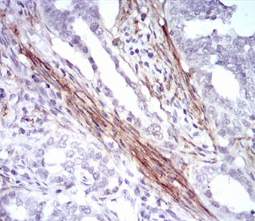

| AC1972 | CNN1 Mouse Monoclonal antibody[1H5B5] | 100ug | $367 | 10days |

| AC1972 | CNN1 Mouse Monoclonal antibody[1H5B5] | 200ug | $660.6 | 10days |